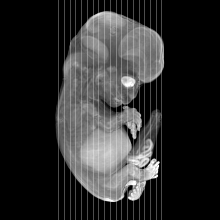

Carnegie Stage 22 (54 post-ovulatory days)

Most embryos at stage 22 are approximately 54 postovulatory days old and measure 25-27 mm in length. Distinguishing criteria for this stage include clear formation of the external ear, the hands begin to extend ventrally beyond the body wall, the fingers of one hand may overlap the fingers of the opposite hand, thickened eyelids just begin to cover the outer margins of the eye, and the superficial vascular plexus of the head now extends about three-quarters of the way above the eye-ear level.

MRI Slice Selector

Mouse: click on a line below to select a view

Finger: tap a line below with a very light touch